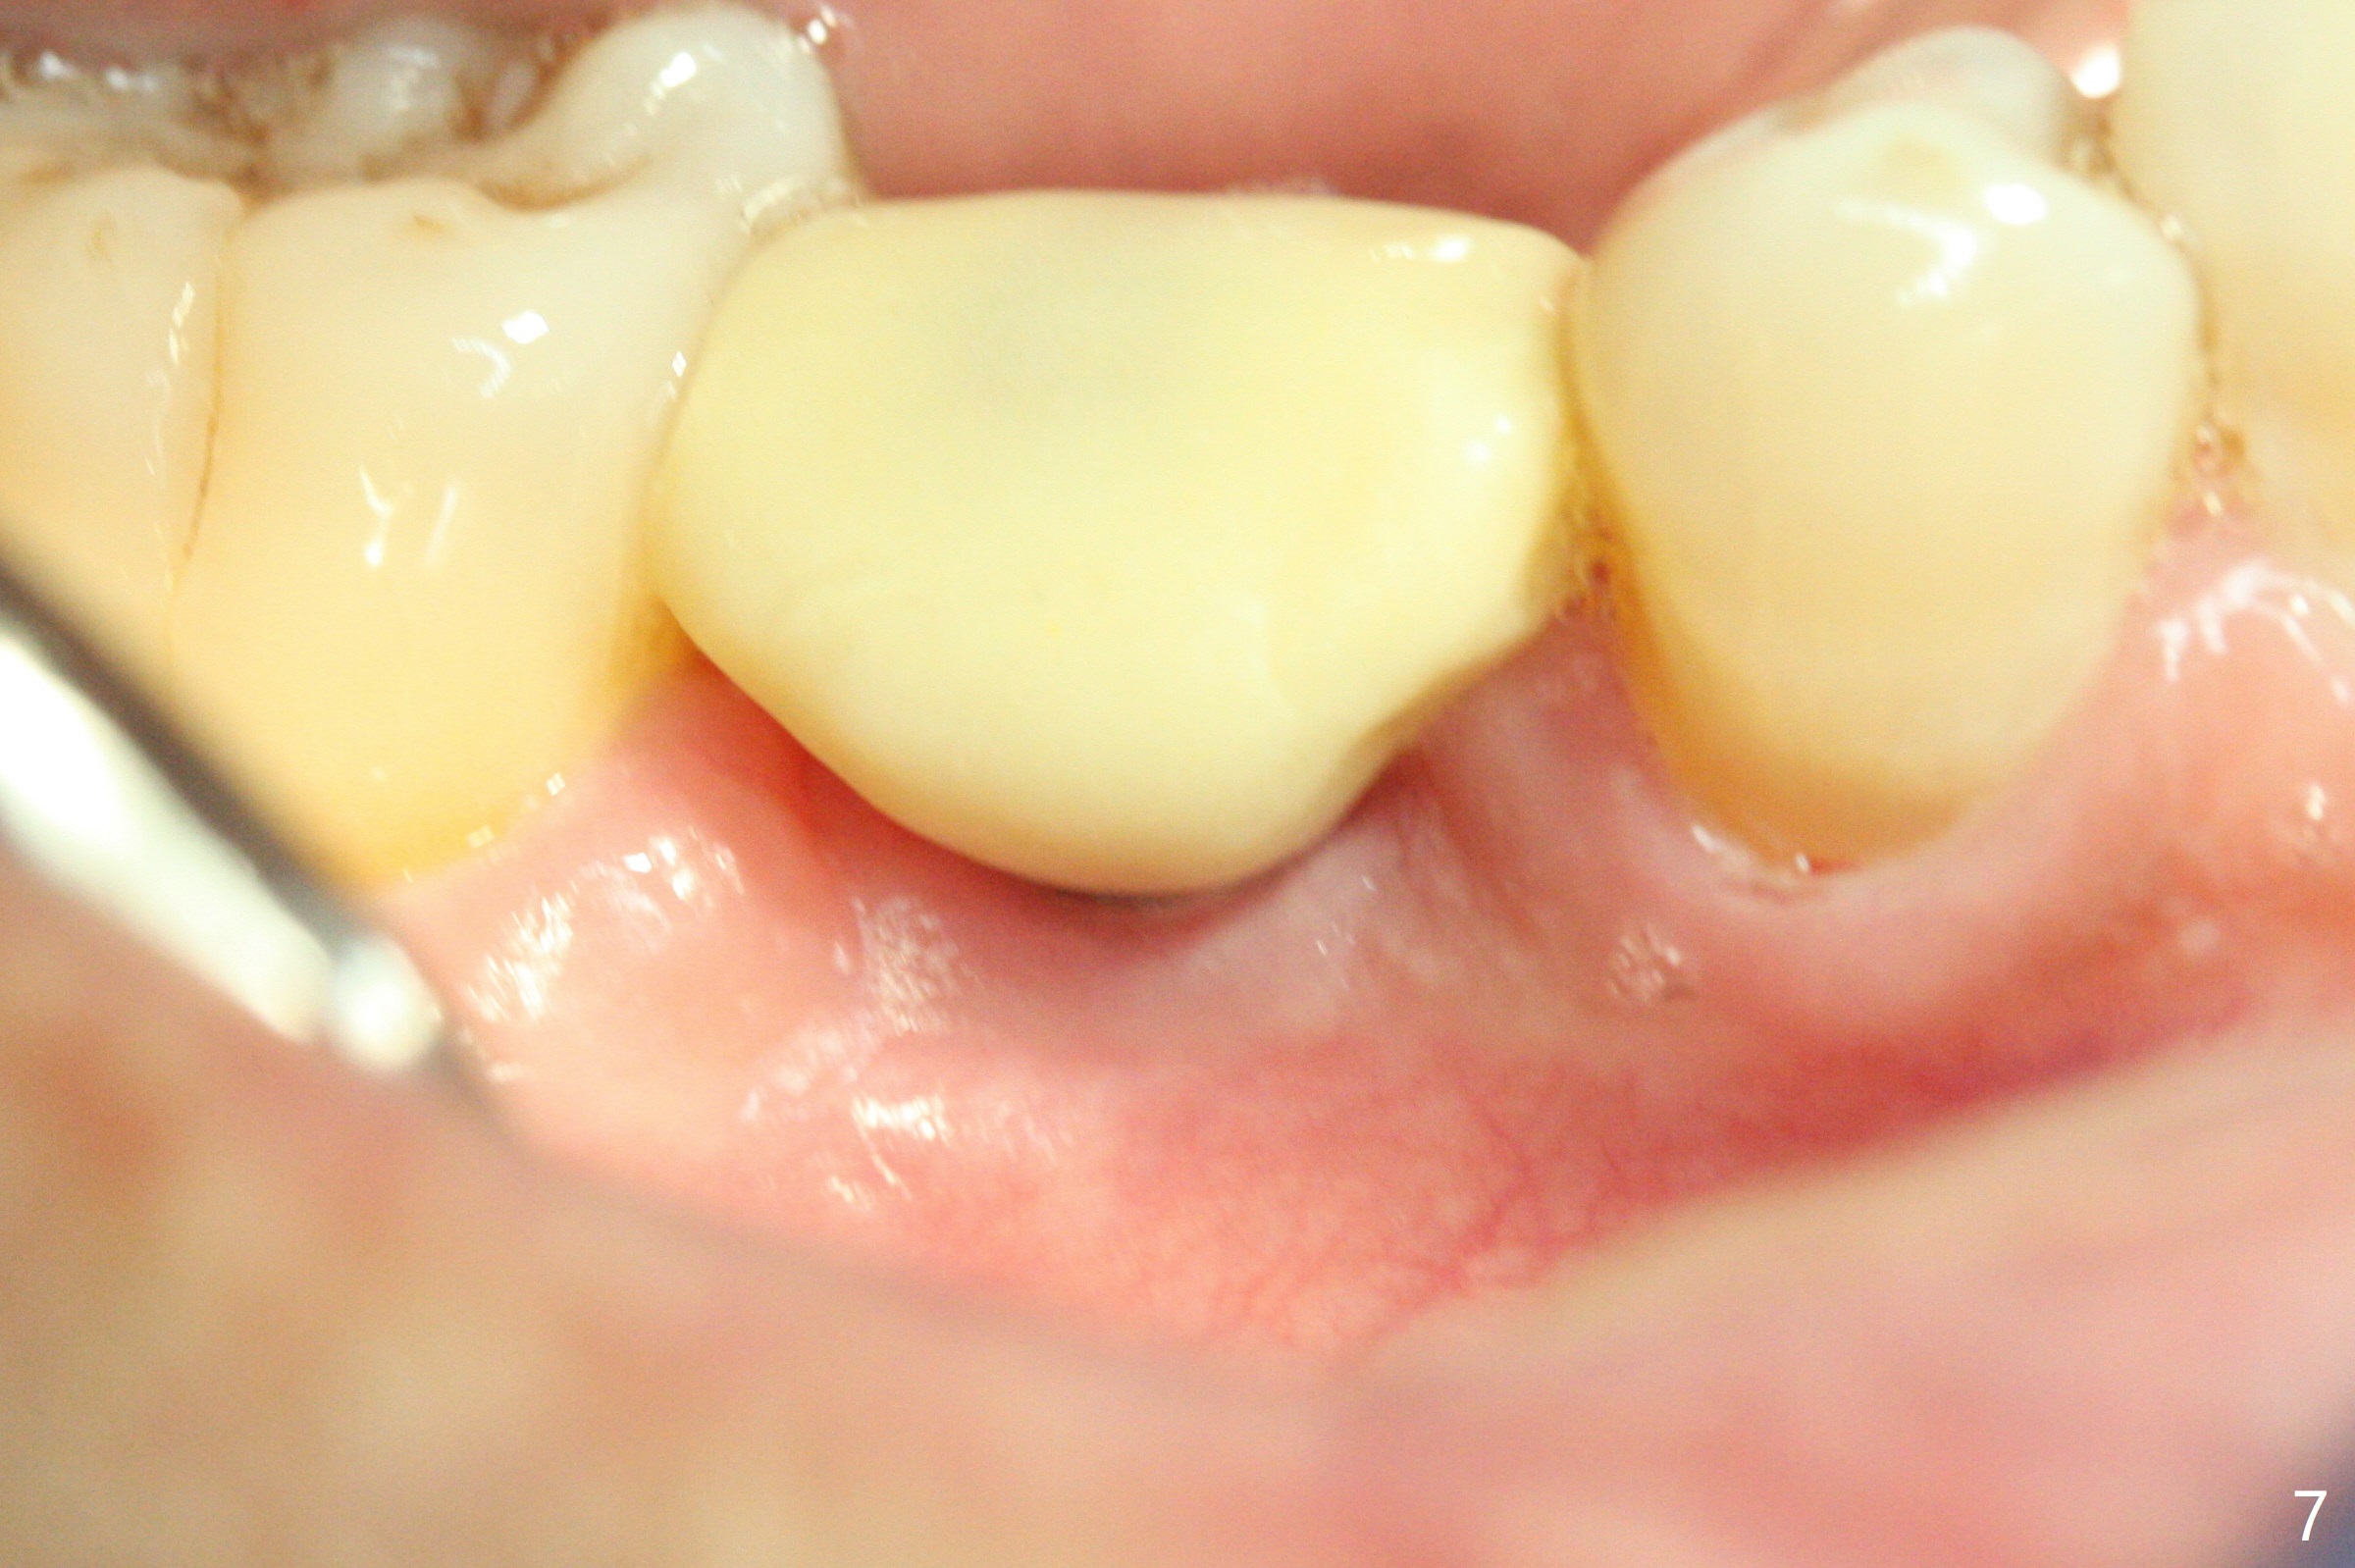

The retained deciduous tooth (lower right 2nd molar, Fig.1 T) has buccal apical infection and recession. After extraction, the initial depth of osteotomy is 11 mm over the flat socket bottom (Fig.2) without visible Mental Loop. Following 3.8 mm Magic Drill for 11 mm, a 4x11 mm dummy implant is placed partially due to hard bone; it appears that the apical osteotomy (Fig.3 yellow outline) overlaps the Mental Loop (red dashed line). For safety, a 4x9 mm IBS implant is placed with insertion torque 40 Ncm; a 5x5.7(4) mm abutment is immediately placed for an immediate provisional to cover the large socket and keep Vera graft in place (Fig.4 *). There is no postop paresthesia, probably due to the fact that the osteotomy is lingual to the Mental Loop. The provisional remains in place 7 days postop; its margin (Fig.5 arrow) covers the socket. The margin of the provisional is trimmed 1 month postop. Impression is taken nearly 3 months postop (Fig.6). The buccal plate looks atrophic 3 months postop (Fig.7 (immediately before cementation)), although there is no sign of periimplantitis. In the future, insert the immediate provisional inside of the buccal gingiva to make the buccal gingiva look bulky instead of buccal to it (Fig.5). The second drawback of placing an implant at the deciduous tooth area is that the crown is wide mesiodistally if orthodontic treatment is not rendered. Although there is lower anterior crowding, the patient declines orthodontic treatment. The bone density around the implant increases 7 months post cementation (Fig.8 *). The higher density bone seems to extend coronally 1 year 7 months post cementation (Fig.9). The dense bone apparently extends toward the abutment as well 3 years 5 months post cementation (Fig.10 curved arrows).